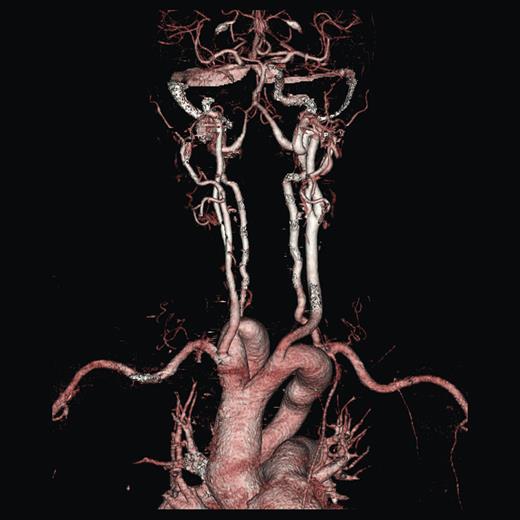

A duplex scan performed on this presentation demonstrated a high, prominent and ectatic aortic arch visible above the sternum, with a diameter of 2.0 cm. The innominate artery appeared ectatic, tortuous with localized wall thickening and had a reported diameter of 1.8 cm. An outpatient computed tomography (CT) angiogram was arranged to help delineate the underlying anatomy. Figure 3 shows a coronal section of this CT angiogram. Figures 4 and 5 show the anterior and posterior views of the 3D reconstruction, respectively.

Figures 3–5 demonstrate a DAA with the right carotid and right subclavian arteries arising from the right-sided arch and left carotid and left subclavian arteries from the left-sided arch. There is also a minor narrowing of the right-sided arch at a kink between the right carotid and subclavian origins. Figure 3 demonstrates both arches rising up into the neck explaining the clinical presentation.